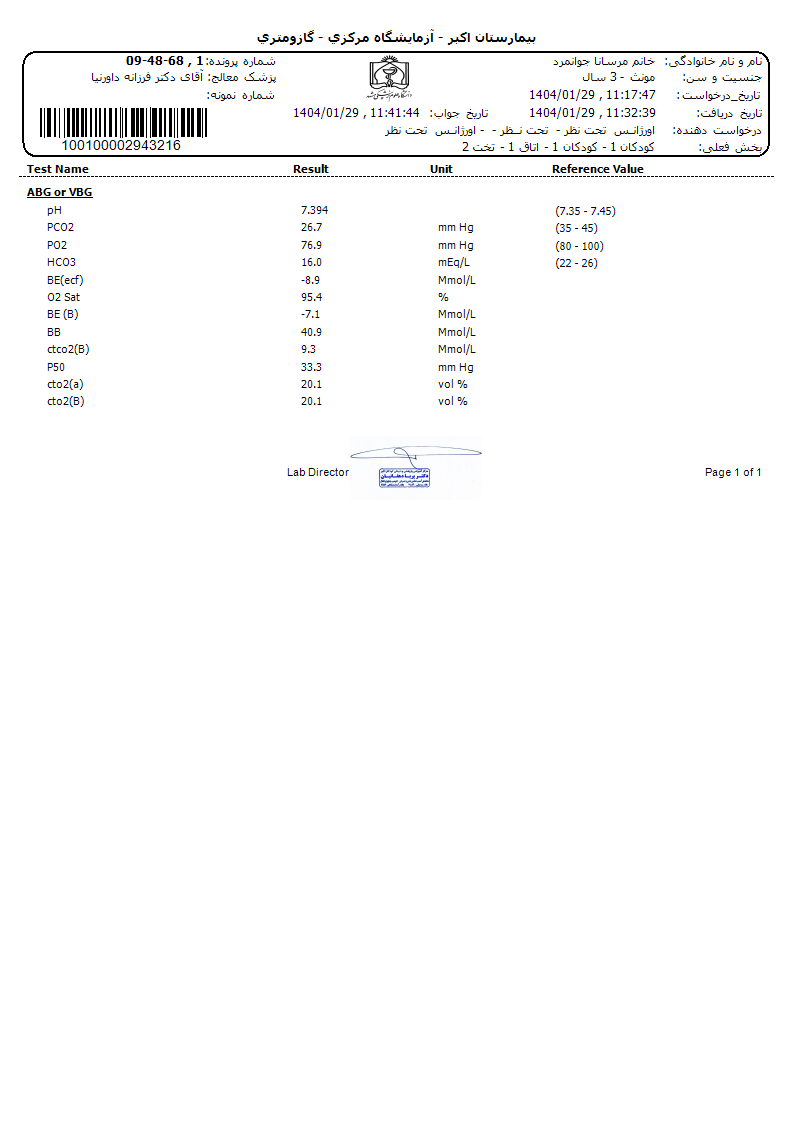

Other: